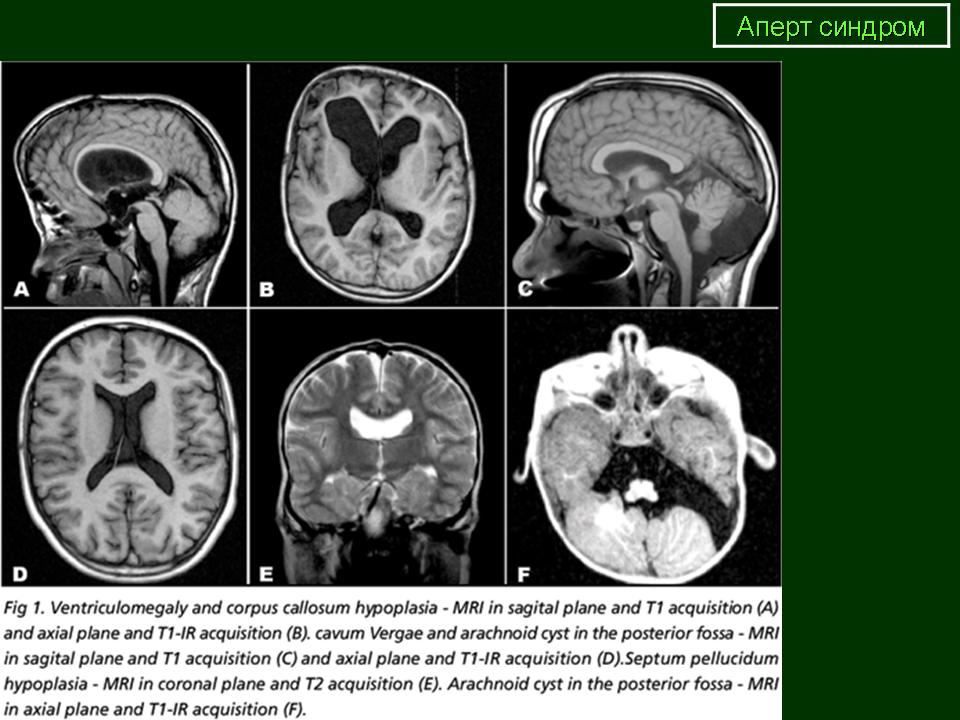

Синдром Аперта - характеризуется дисморффией лицевого скелета, акроцефалосиндактилией, врожденным пороком развития черепа (башенный череп). Гипертелоризм, широкий корень носа, щелевидная форма носа, высокое неба, ращелина язычка. Макрогнатия верхней и микрогнатия нижней челюстей. Плоские орбиты глаз и экзофтальм, антимонголоидный разрез глаз. Заболевание может передаваться по наследству.

Синдром Аперта проявляется брахиоцефалией, уплощением лица с гипертелоризмом, косоглазием, параличом глазных мышц и гипоплазией верхней челюсти. У таких пациентов отмечаются выраженный экзофтальм, короткая скуловая дуга и вдавленная теменная область. Часто такие пациенты рождаются с синдактилией на руках или на ногах. Нёбо при синдроме Аперта - узкое с углублением по середине, в ряде случаев имеется расщелина нёба.

Форма головы при синдроме Аперта соответствует бикоронарному синостозу. При исследовании черепа было выяснено, что деформация развивается не из-за краниосиностоза, а скорее из-за снижения способности к росту основания черепа, что приводит к преждевременному сращению среднелинейных швов от затылка до спинки носа, а также к выраженной деформации верхней и нижней челюстей.